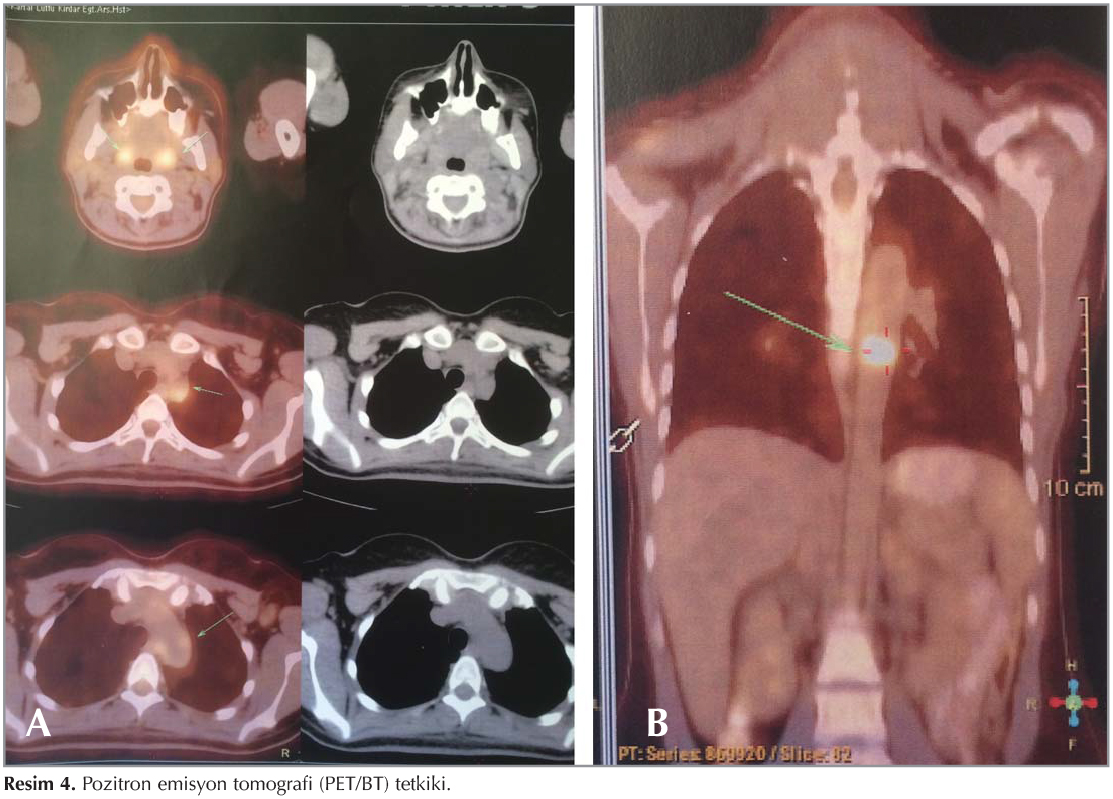

Laboratuvar incelemelerinde, l?kosit 8.2 ? 109/mm?, hemoglobin 10.21 g/dL, eritrosit sedimantasyon hızı (ESH): 120 mm/sa, C-reaktif protein (CRP): 59.9 mg/dL bulundu. Kan biyokimyasal incelemeleri ve tam idrar tetkiki normal sınırlarda idi. Toraks BT'de herhangi bir patolojiye rastlanmadı (Resim 1). Olguya yapılan fiberoptik bronkoskopi (FOB)'de, trakea ve her iki ana bronşta yaygın mikronod?ler lezyonlar g?r?ld? (Resim 2). Bronkoskopik lavajda asido-rezistan bakteri (ARB) menfi, histopatolojik incelemede gran?lomat?z inflamasyon saptandı (Resim 3). PPD'si 12 mm ?l??len hastanın, quantiFERON testi negatif saptandı. Bu bulgular eşliğinde olguya t?berk?loz tedavisi başlandı. T?berk?loz tedavisinin 1. ay kontrol?nde ateş ve diğer şikayetlerin devam ettiği, CRP ve ESR değerlerinin artmış olduğu g?r?ld?. Bu arada t?berk?loz, mantar ve diğer infeksiyon ajanları i?in bakılan k?lt?rler negatif kaldı. Kan k?lt?rlerinde herhangi bir ?reme olmadı. Yaygın eklem ağrıları eklenen olgunun bağ doku hastalıklarına ait bakılan otoimm?n antikorları ve malignite t?m?r belirleyicileri normal sınırlarda saptandı. Serum ACE seviyesi normaldi, g?z kons?ltasyonunda patolojiye rastlanmadı. Kardiyoloji kons?ltasyonunda ekokardiyografik değerlendirilme normal bulundu. Sebebi bilinmeyen ateş (SBA) etyolojisi araştırılmak ?zere yapılan kemik iliği biyopsi, serum protein elektroforezi sonu?larında, batın tomografik incelemelerde ve gastroskopik, kolonoskopik değerlendirilmelerde de patolojik bulguya rastlanmadı. T?m bu incelemeler neticesinde herhangi bir patolojik bulguya rastlanmaması ?zerine, SBA araştırılmak ?zere 18-fluorodeoksiglukoz kullanılarak pozitron emisyon tomografi (PET/BT) tetkiki yapıldı (Resim 4). PET değerlendirilmesinde, arkus aortada ve T7 vertebra d?zeyinde daha belirgin olmak ?zere torasik desenden aortada dif?z hipermetabolik g?r?n?m saptandı ve olası vask?lit y?nden klinik ve laboratuvar verileriyle birlikte değerlendirilmesi ?nerildi. Olgunun g?ğ?s ve boyun MR anjiyografisinde aortada proksimalde, sol subklavyen arter orifisi d?zeyinden başlayarak distalde torakal aorta yaklaşık orta seviyesine kadar uzanan, 5 mm kalınlığına ulaşan ve anlamlı stenoz oluşturmayan konsantrik duvar kalınlaşması saptandı. Abdominal aorta ve dallarına y?nelik doppler ultrasonografik incelemesi normaldi. Mevcut bulgular ile değerlendirildiğinde olguya Takayasu arteriti (TA) tanısı konuldu. Romatoloji kliniğince ilk g?n 1500 mg y?kleme dozunda prednol başlandı. İkinci g?nden itibaren 50 mg prednol ve haftada bir me-? totreksat (MTX) ile tedaviye devam edildi. Tedavinin 1. haftasında olgunun klinik tablosu tamamen d?zelirken, kontrolde ESR değeri 9, CRP 0.01 mg/dL saptandı. Olgumuz halen takip altında olup, kliniği stabildir ve kortizon tedavisi devam etmektedir.

Tanıda anjiyografi altın standart olsa da, son yayınlar BT ve MR gibi invaziv olmayan g?r?nt?leme metodlarının anjiyografi kadar etkin olduğunu g?stermiştir (1,5). Hatta PET-BT'nin erken tanıda MR anjiyografi ve arteriografiden ?nce ?nemli ek bilgiler sağladığı tespit edilmiştir. Duyarlılığı %92, ?zg?ll?ğ? %100 olarak bildirilmiştir (1,5,17,18). Olgumuzun PET/BT'sinde, arkus aorta ve desenden aortada vask?litle uyumlu dif?z hipermetabolik tutulum saptanması ?zerine TA tanısına gidildi.